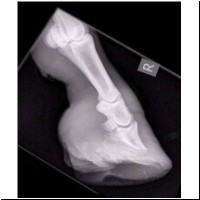

rechter Vorderhuf,

von vorne, nach der Behandlung

Der rechte Vorderhuf nach der Behandlung. Die Fraktur ist gut verheilt. Bei der nächsten Hufkorrektur zeigte sich das Ablösen der Hornsohle. Darunter hatte sich bereits eine neue Sohle gebildet. Durch die Hufbeinfraktur konnte der Hufmechanismus nicht arbeiten und die Sohle wurde in der Zeit minder versorgt. Das zeigt, wie wichtig es ist, den Hufen stets den korrekten Stand zu geben. Jede unfachmännische Korrektur kann zu Schäden im Gelenk und Störungen im Huf bzw Hufstoffwechsel führen.